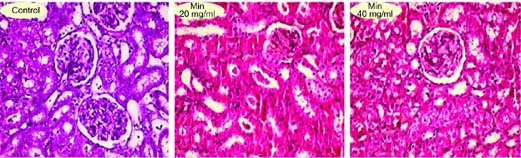

Significant interstitial inflammation and tubular atrophy were evident in the kidneys of Mn 20 and 40 mg/mL groups (Figure 4 and Table 3). Moreover, Mn 40 mg/mL caused renal tissue necrosis (Figure 4 and Table 3).

Figure 4. Kidney tissue histopathological alterations in manganese-exposed animals. Hematoxylin and eosin staining. The grades of histopathological changes are given in Table 3.

Table 3. Renal tissue histopathological alterations in manganese-exposed rats.

Interstitial inflammation Tubular atrophy Necrosis

Control

Manganese 20 mg/mL + + +

Manganese 40 mg/mL ++ ++ +++

+: Mild; ++: Moderate; and +++: Severe histopathological alterations.